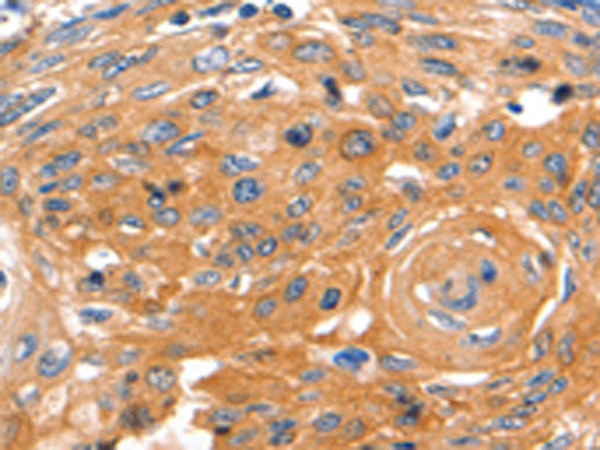

分类: 科研抗体货号: P07194别名: HER3; FERLK; LCCS2; VSCN1; ErbB-3; c-erbB3; erbB3-S; MDA-BF-1; c-erbB-3; p180-ErbB3; p45-sErbB3; p85-sErbB3应用: IHC反应种属: Human, Mouse, Rat